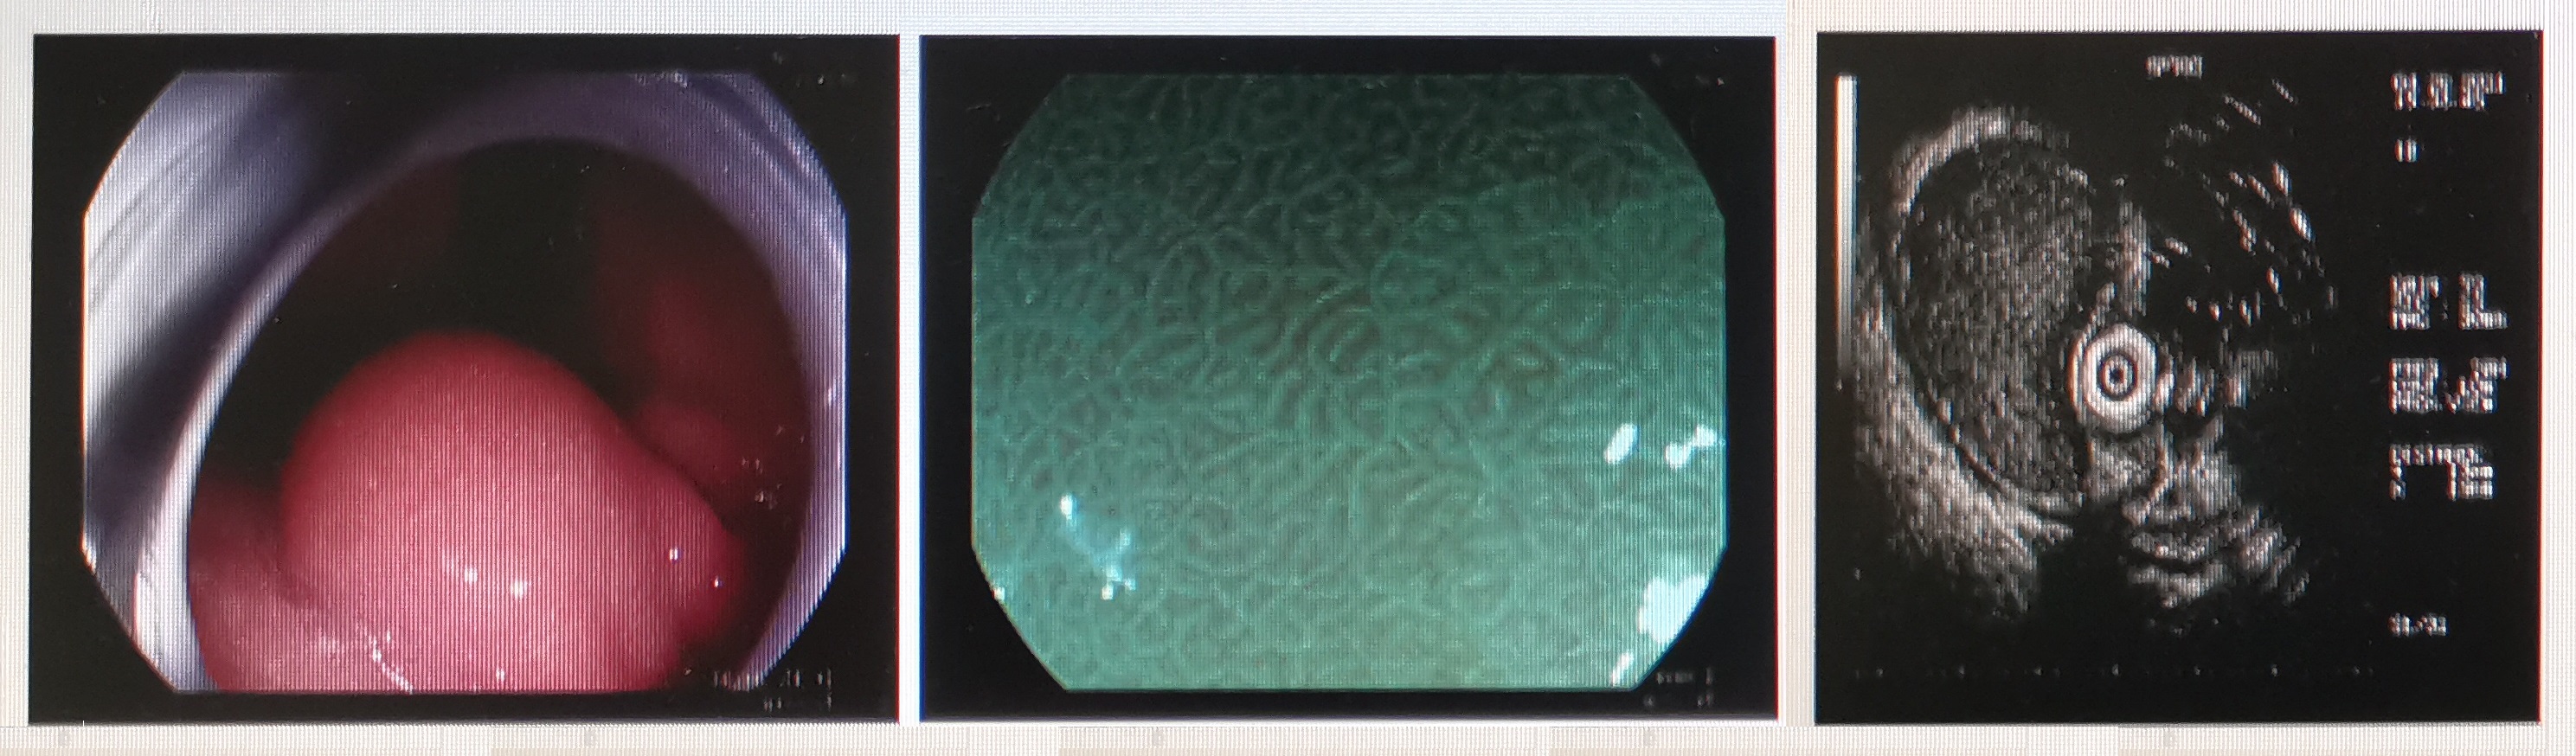

超声内镜在上世纪70年代末诞生于日本,是将内镜检查和超声波检查相结合产生的一种新的内镜技术,在开发之初主要用于探查胃壁的层次结构,随着不断地改良,目前超声内镜已经成为消化内镜领域的一项成熟技术,在临床中不仅可以用于消化道和胰胆系统疾病的诊断,还可以在超声内镜下进行相应的治疗。

超声内镜的优势在于可以对位于消化道黏膜下甚至消化道管壁外等无法进行直视观察的病灶进行超声探查,获取其回声特点和起源层次,然后进行性质评估,可以说是临床医生的“第三只眼”,称之为镜界“二郎神”也丝毫不为过。

1、大超声:主要用于胰胆系统疾病的诊断和治疗,使用的内镜是头端有固定超声发射装置的特殊内镜,发射的超声波频率低,波长长,可以观察更大的范围,一般用于消化道管壁外相邻脏器或病变的探查,可进一步分为“环扫”和“扇扫”2种观察方式,前者主要用于检查病变,后者可以用于内镜下穿刺介入治疗的引导。

2、小超声:主要用于消化道管壁病变的诊断,操作时需要将超声小探头经内镜活检孔道放置到病灶的旁边,发射的超声波频率高,波长短,可以获得更精细的图像,一般用于食管和胃肠道管壁来源病变的探查。